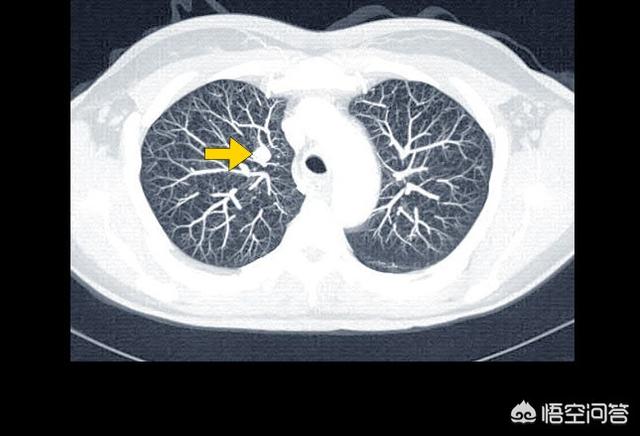

一般に、我々の医学では、がん細胞が常に気管支や肺胞の最上層にあり、それ以上細胞の最下層に浸透していない場合、この種のがんはin situがんと呼ばれ、実際に通常の健康診断で多くの人が発見している。

現時点では、in situがんはまだ悪性腫瘍ではないので、健康診断で発見されたら、ただちに摘出し、病理検査を行って悪性か良性かを判断し、系統的な分析を行って判断する必要がある。

しかし、多くの肺癌患者はこのin situ癌を簡単に無視し、時間の経過とともにこのin situ癌は気管支の内壁や気泡に浸潤し、完全な浸潤癌を形成する。一旦このような癌に罹患すると、人体はこの種の癌に苦しむことになる。